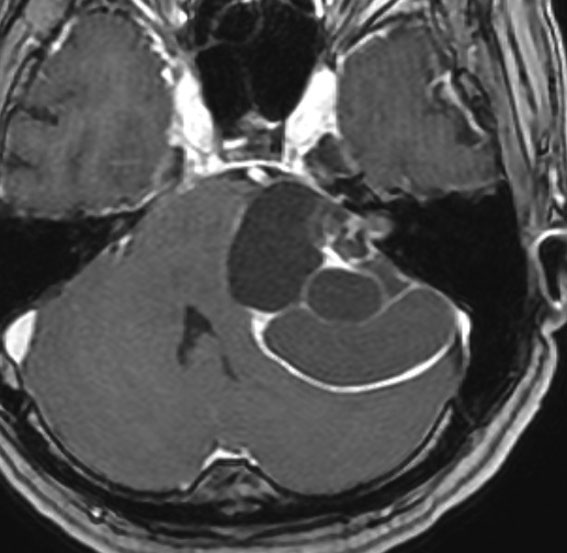

定位分割放射線治療をした聴神経腫瘍の例(左)。20%くらいの確率で放射線治療後に一時的に大きくなることがあります(中央)。やがて小さくなっていきます(右)。放射線治療後に腫瘍が大きくなっても,あわてて手術を受け入れてはいけません。

この画像はMRIのCISS/FIESTA画像というのを用いています。造影剤を使わないでも腫瘍の形と大きさが精密に解るので,経過観察には適している検査法です。

2001年に治療をした,40代女性の大きな聴神経腫瘍です。50グレイ25分割の定位放射線治療を行いました。中央が1年後,右が3年後です。徐々に縮小して手術を必要としませんでした。このサイズの聴神経腫瘍でも放射線治療は選択できるのですが,多くの場合は開頭手術をお勧めするサイズとも言えます。